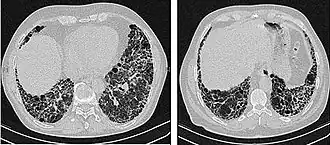

The radiological evaluation through HRCT is an essential point in the diagnostic pathway in IPF. HRCT is performed using a conventional computed axial tomographic scanner without injection of contrast agents. Evaluation slices are very thin, 1–2 mm (0.039–0.079 in).

Typical HRCT of the chest of IPF demonstrates fibrotic changes in both lungs, with a predilection for the bases and the periphery. According to the joint ATS/ERS/JRS/ALAT 2011 guidelines, HRCT is an essential component of the diagnostic pathway in IPF which can identify UIP by the presence of:[3]

• Reticular opacities, often associated with traction bronchiectasis

• Honeycombing manifested as cluster cystic airspaces, typically of comparable diameters (3–10 mm (0.12–0.39 in)) but occasionally large. Usually sub-pleural and characterized by well-defined walls and disposed in at least two lines. Generally one line of cysts is not sufficient to define honeycombing

• Ground-glass opacities are common but less extensive than the reticulation

• Distribution characteristically basal and peripheral though often patchy.

High-resolution computed tomography scans of the chest of a patient with IPF. The main features are of a peripheral, predominantly basal pattern of coarse reticulation with honeycombing